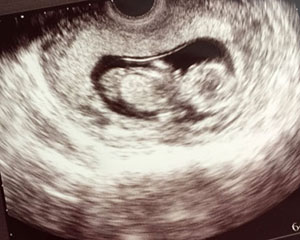

おなかの赤ちゃんが順調に育っているか、またお母さんの体調が良好かどうかを、超音波機器なども用いてチェックいたします。妊娠中は身体にいろいろな変化が起こりますし、自覚症状が無くて一見順調に見えても、トラブルが隠れているケースもあります。

初診時/内診、血圧、尿蛋白、尿糖、超音波検査、体重

毎回/超音波検査、体重測定・血圧測定、尿蛋白・尿糖・浮腫

※妊娠12週頃までは経腔超音波を行います。それ以降は経腹超音波での検査になります。